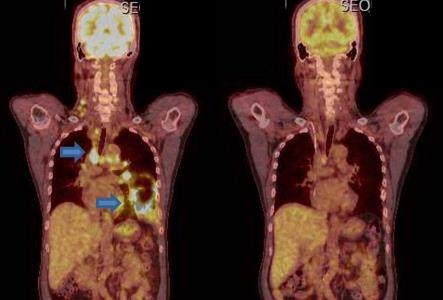

폐암은 원발성 폐암을 말하며 원발성 폐암은 폐에서 기원하는 악성 종양을 말한다. 폐로 전이된 암은 폐로 전이된 것으로 분류되며, 폐암이라기 보다는 기원 장기로 전이된 것으로 분류된다. 폐암은 조직학적 유형에 따라 크게 소세포폐암과 비소세포폐암으로 분류된다.

이 분류의 이유는 소세포 폐암이 치료 및 예후 측면에서 다른 유형의 폐암과 확연히 다른 특징을 가지고 있기 때문입니다.

이러한 폐암의 원인으로 인해 폐암으로 진단되기 전에 폐암 초기증상을 조기에 발견하면 다른 장기로의 전이나 진행성 폐암으로의 진행을 어느 정도 지연시키거나 적절하게 치료할 수 있지만 일반적으로 폐암의 초기 단계는 특별한 징후나 증상이 없으므로 조기에 발견하는 경우는 극히 드뭅니다.